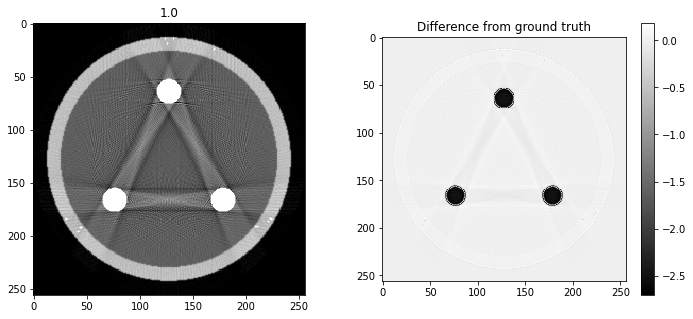

# Question 12

search = np.linspace(0,1,11)

for alpha in search:

rec = out+alpha*reproj

f,ax = plt.subplots(1,2,figsize=(12,5))

ax[0].imshow(rec,vmin=0,vmax=0.5)

ax[0].set_title(alpha)

im = ax[1].imshow(img[80]-rec)

f.colorbar(im,ax=ax[1])

ax[1].set_title('Difference from ground truth')

plt.show()